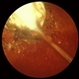

- Cysticercus Toxocara

- toxocariasis, cysticercosis

- 30-year-old female, HM; 20/20; later (2/1/90) 20/50 OD.